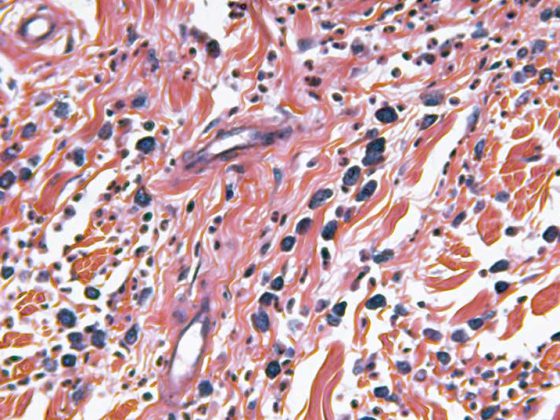

Die Behandlung von Patienten in Lungenkliniken kann neben der Diagnostik und Therapie auch die Begleitung im Sterben beinhalten. Bei den nicht-intensivmedizinisch betreuten Patienten sind neben dem Lungenkarzinom v.a. die COPD sowie die Lungenfibrose die Erkrankungen, die am häufigsten zum Tode führen.